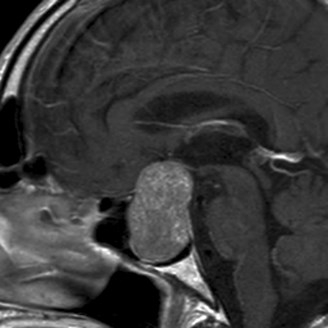

De hypofyse is een kleine klier onderaan de hersenen die instaat voor de productie van tal van hormonen. Soms ontwikkelen zich hier goedaardige tumoren, adenomen genaamd. Hiervoor is soms chirurgische behandeling nodig. Zeker als deze tumoren groot worden en op de oogzenuwen gaan drukken of als deze tumoren teveel hormoon gaan produceren. Dit is bijvoorbeeld zo bij de ziekte van Cushing ( te veel cortisol ) of bij acromegalie ( te veel groeihormoon ).

Operaties aan de hypofyse worden tegenwoordig meestal via een kijkoperatie verricht langs de neus ( endoscopische hypofyse ingreep ) in samenwerking met een neus-keel-oor arts. Door deze nieuwe techniek is er geen insnede noodzakelijk en is de last door de ingreep sterk gedaald.

Ook andere tumoren van de schedelbasis of de hersenen kunnen endoscopisch langs de neus worden behandeld. Bijvoorbeeld kwaadaardige tumoren van de neus of sinussen (sinuscarcinoom), craniopharyngiomen of meningiomen van de voorste schedelgroeven. De endoscopische transnasale techniek vermijdt dat de schedel van bovenaf dient opengemaakt te worden en heeft tot doel om gezond (hersen-)weefsel zo maximaal mogelijk te beschermen.